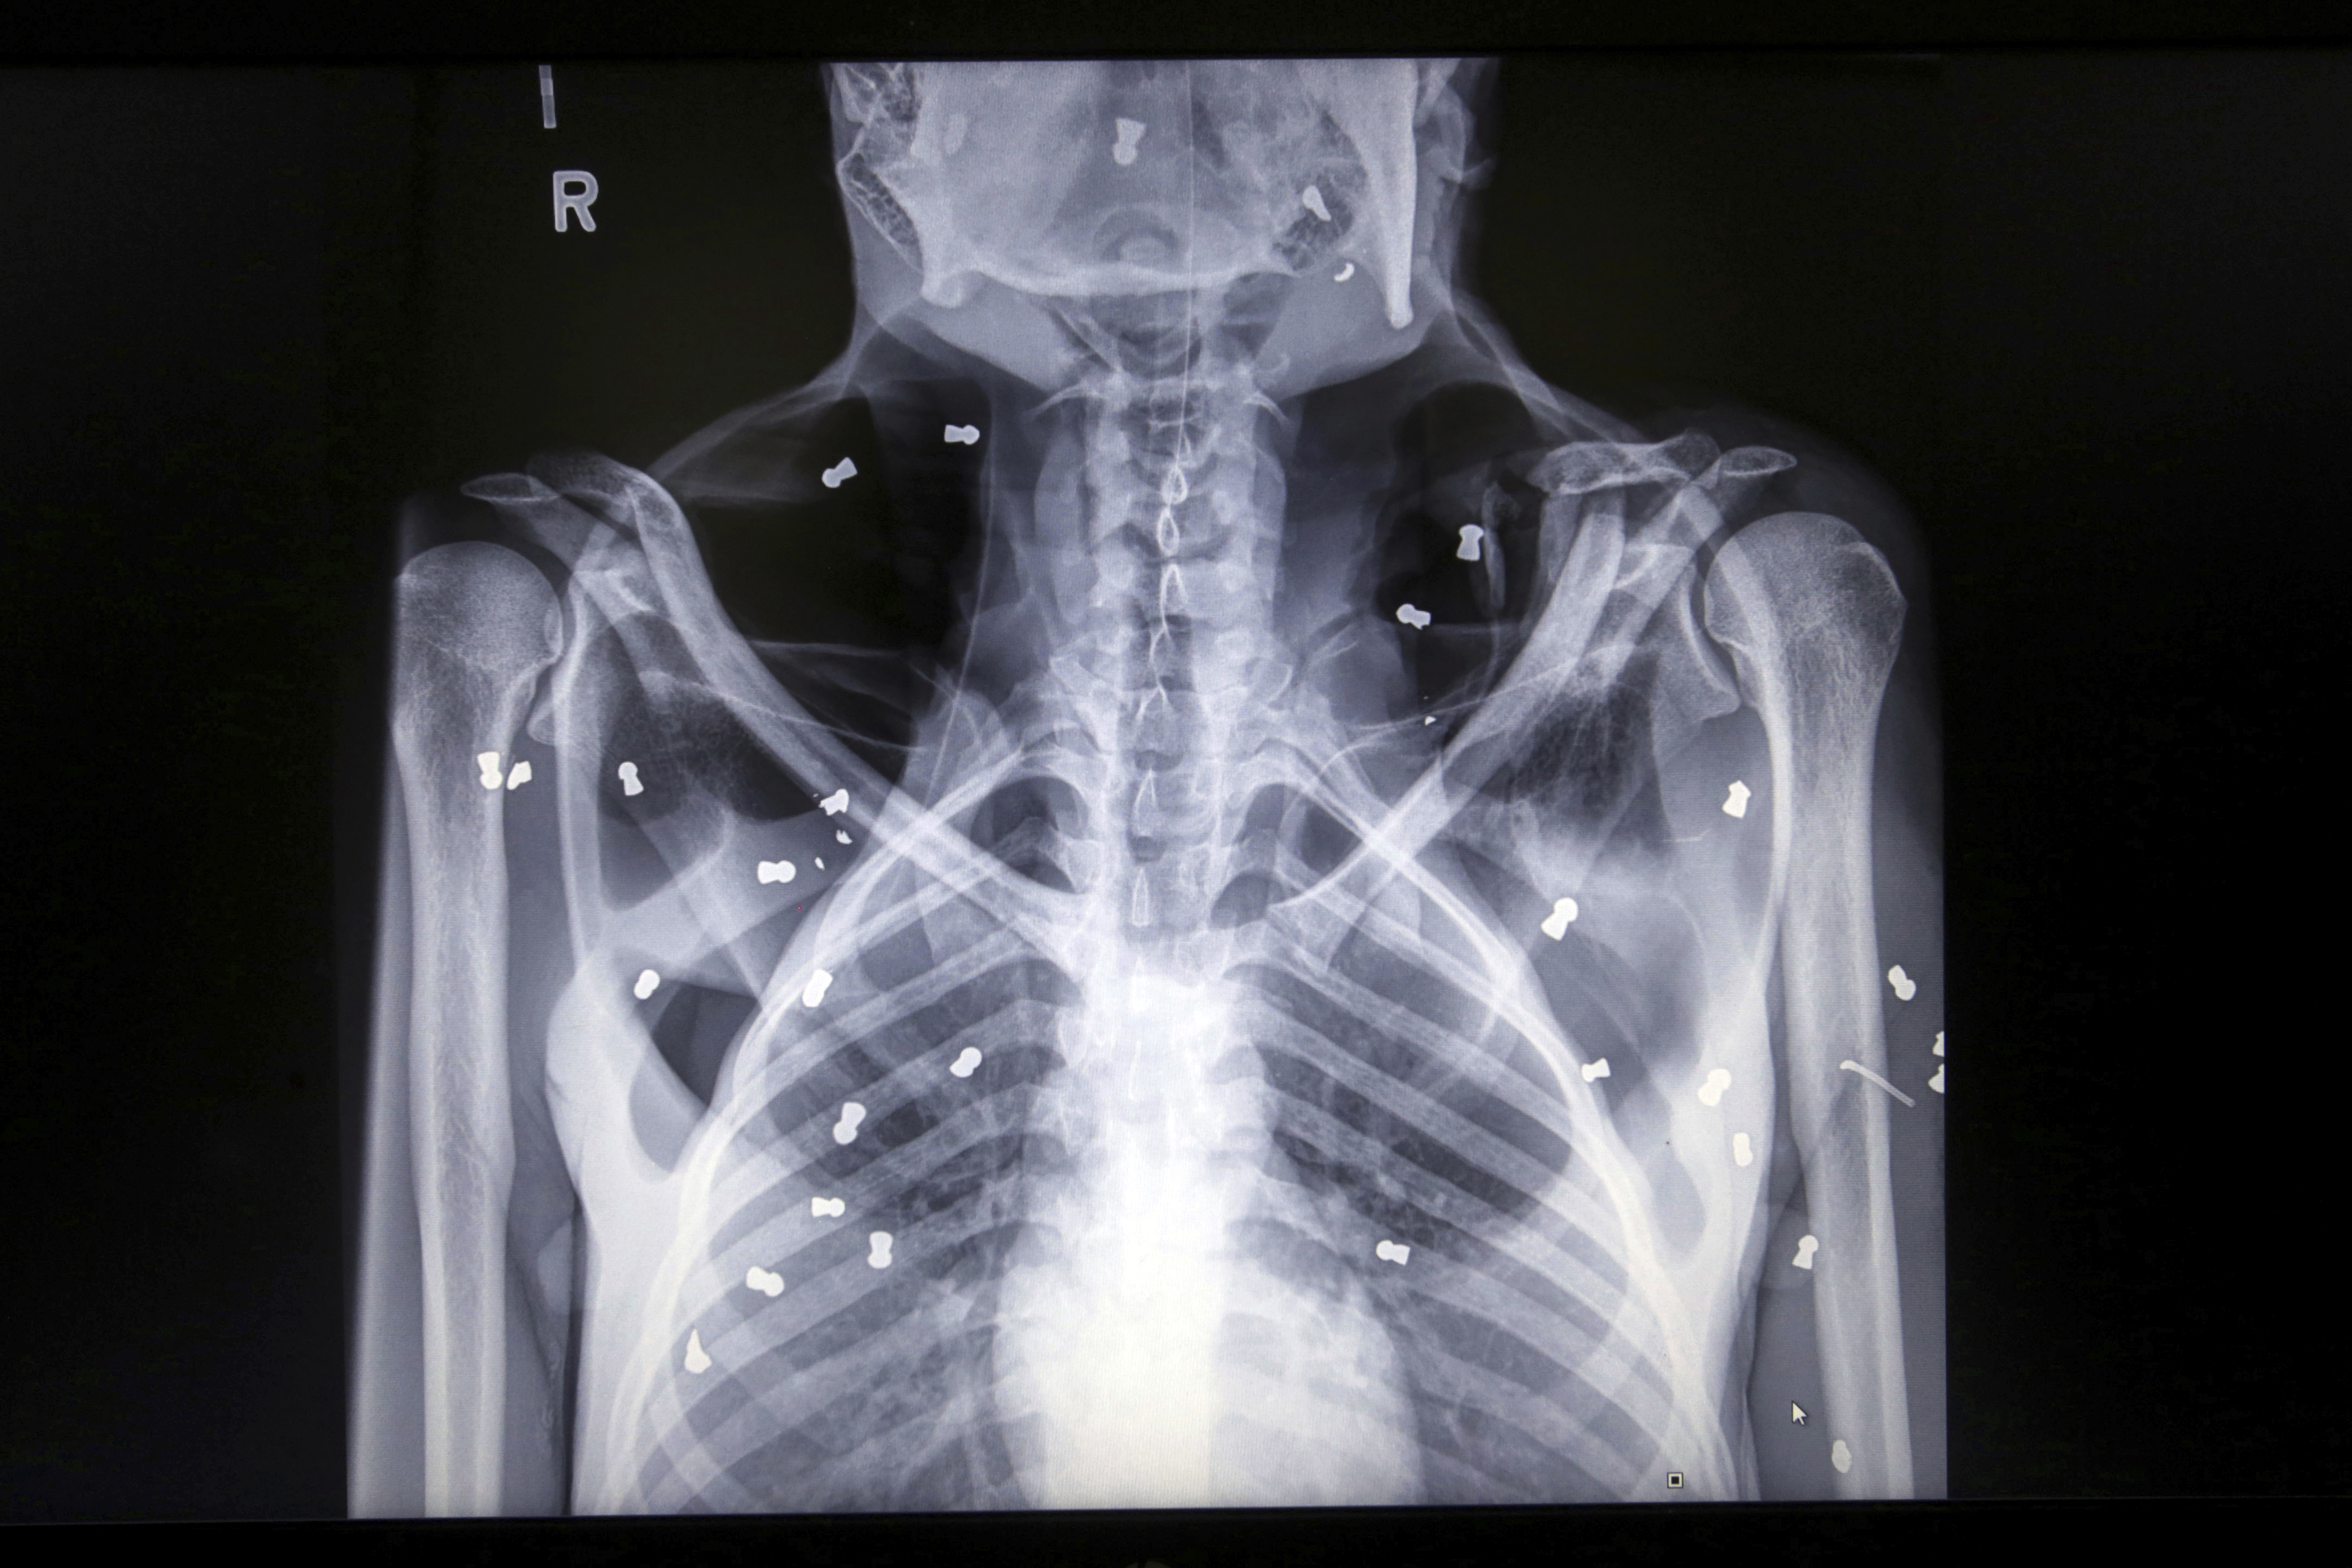

В Индонезии обнаружили самку орангутана, которая выжила, получив 74 пулевых ранения. Предположительно животное расстреляли из пневматического ружья на местной ферме, пишет The Straits Times.

Орангутана заметили в провинции Ачех. С самкой находился детеныш, который также получил ранения, но не выжил.

Самку, которой дали кличку Хоуп, забрали в центр для животных, где она проходит реабилитацию. В настоящее время она уже может самостоятельно есть.